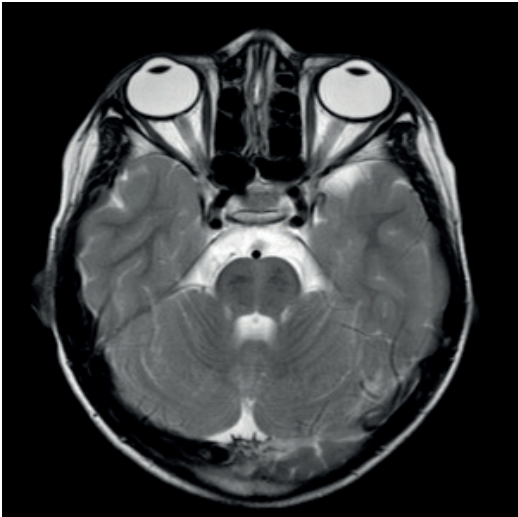

- Cerebelite Aguda: Geralmente de etiologia pós-infecciosa (viral) ou pós-vacinal, com destaque para a família Herpes vírus (Varicela-Zóster, EBV). O curso tende a ser benigno e autolimitado, embora a Ressonância Magnética (RNM) possa evidenciar alterações. O uso de Aciclovir é controverso e geralmente reservado para formas graves.

- ARSACS (Ataxia Espástica de Charlevoix-Saguenay): Caracteriza-se por ataxia associada à espasticidade. A RNM demonstra atrofia do vérmis superior e estrias pontinas lineares características.